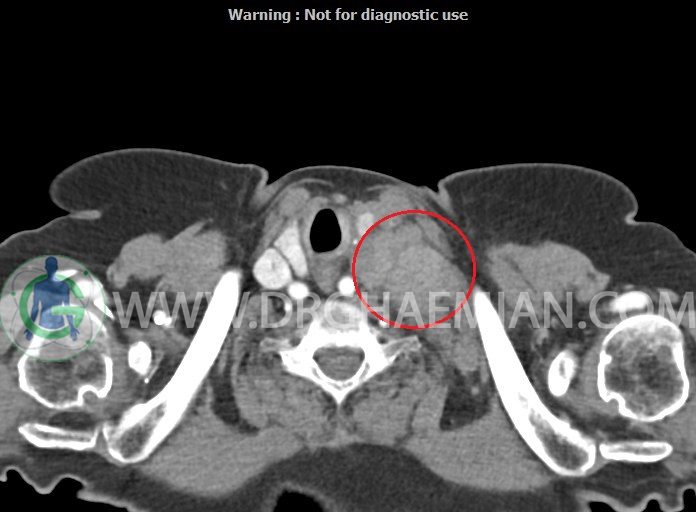

در سی تی اسکن اسپیرال از گردن با تزریق (مولتی دیدکتور 16 با مقاطع ظریف و بازسازی های ساژیتال و کرونال):

– تصویر توه های نسج نرمی oval shape متعدد با Enhancement تقریباً هوموژن، قرار گرفته در سمت چپ گردن، در لول غضروف کریکوئید با اثر فشاری شدید و compression ورید ژوگولار، با گسترش تحتانی به اینفراکلاویکولار چپ، به حداکثر ابعاد 28x50mm (با Enhancement مختصر هتروژن در این توده)

در درجه اول مطرح کننده لنفادنوپاتی متاستاتیک مطرح می باشد بالین، تومورهای منشأ گرفته از غلاف عصبی زنحیره سمپاتیک چپ گردنی، شبکه براکیال و لنفوم نیز در DDX قرار دارند. لذا نمونه برداری بافتی جهت بررسی بیشتر توصیه می شود.

– اسکولیوز مهره های سرویکال با تحدب به راست، احتمالاً در زمینه اثر فشاری توده های مذکور

مشهود است.